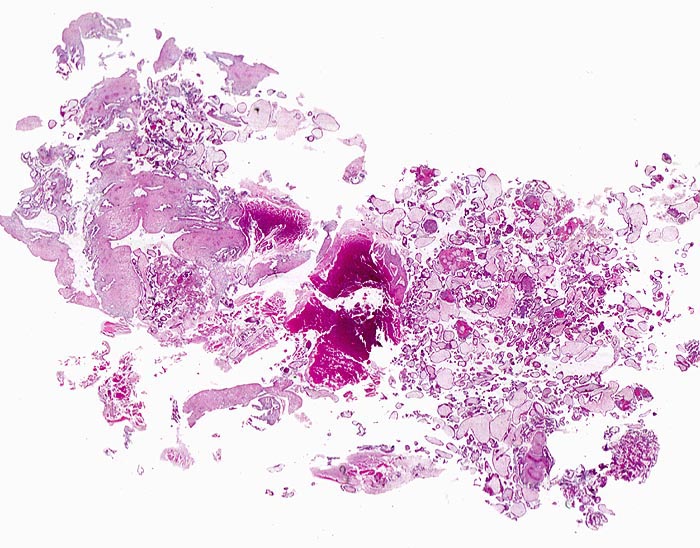

Basel 3BA FS/ Abortmaterial Frühschwangerschaft (Kurettage)

Abortmaterial Frühschwangerschaft (Kurettage)

Plazenta

Makroskopie

Befund